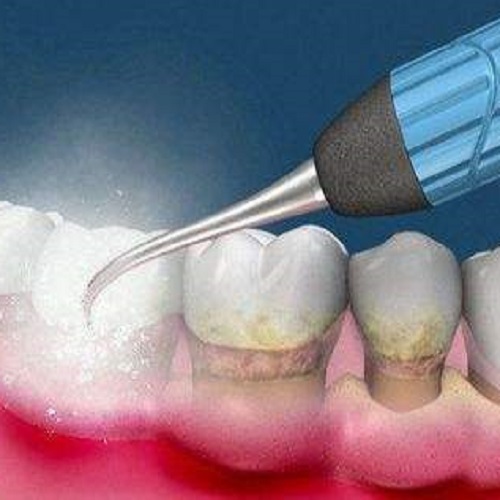

Shenzhen VickongDental Dentist recommends: Adults should have their teeth cleaned every six months to a year. Regular cleaning can remove tartar, plaque and other dirt and prevent the occurrence of oral diseases. Teeth cleaning can also treat initial periodontitis and protect dental health.

In addition, teeth cleaning can also be used as part of a comprehensive oral examination to detect dental problems in time. However, for smokers, people with tea drinking habits, and periodontitis patients may need more frequent cleanings.